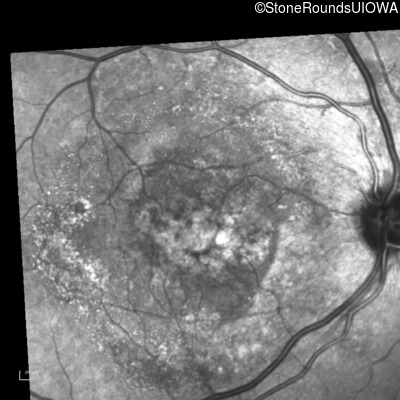

Infrared Fundus Photograph - Left - 20/30

Exemplar